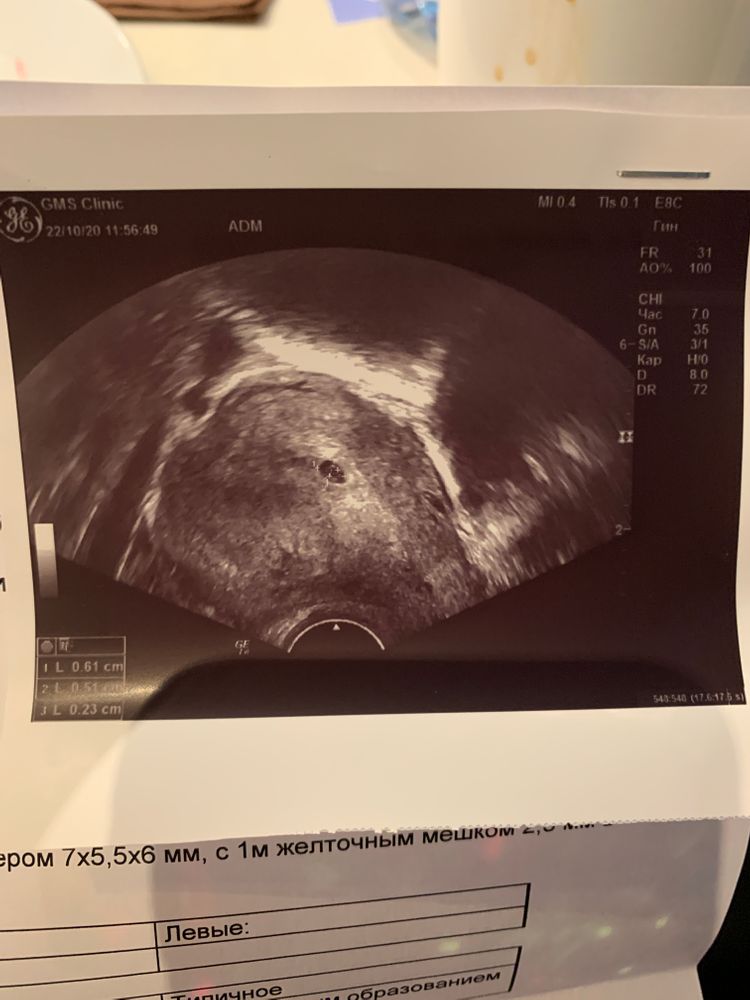

СчастливыВместе, cпасибо 💐 тоже надеялась на хороший конец 🙏🙏 но вчера вечером живот болел и сегодня в дневник хотела сердечко поставить , потом думаю, нет лучше не буду за ранее и день сегодня плохой.. пошла на узи а там все 😢